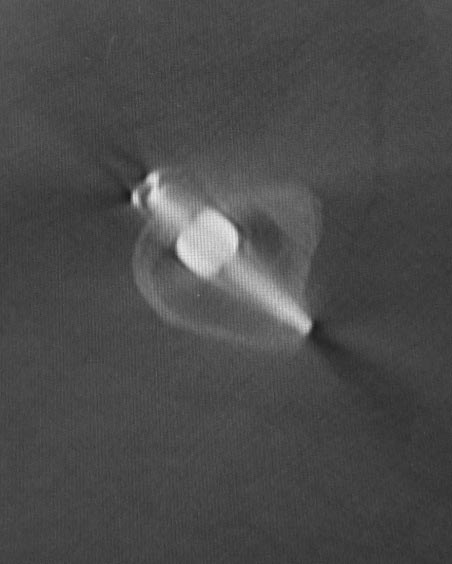

Уважаемые коллеги. Хотелось бы выслушать мнения и советы по представленному случаю. Пациент 42 лет, вес 130 кг, рост около 160 см, сахарный диабет в легкой форме (впервые выявлен после травмы). Травма в феврале 2011 г. - упал с мотоцикла на отдыхе за рубежом. По возвращении в Россию был прооперирован в несколько этапов: в марте 2011 г. - остеосинтез обеих костей правого предплечья пластинами по поводу открытого перелома; интрамедуллярный остеосинтез правого бедра; остеосинтез проксимального конца правой большеберцовой кости. В апреле 2011 г. был доставлен 1 блокирующий винт в дистальное отверстие гвоздя и выполнена пластика крестообразных и наружной боковой связок левого коленного сустава. В феврале 2012 г. были удалены фиксаторы с проксимального конца правой большеберцовой кости и выполнена пластика крестообразных и наружной боковой связок правого коленного сустава. За это время пациент смог начать ходить, сначала с костылями, а затем - без дополнительной опоры. Летом 2013 г. решил укрепить ноги с помощью подъемов пешком на пятый этаж. В результате - усталостная рефрактура правого бедра и перелом интрамедуллярного гвоздя. 09.09.2013 - реостеосинтез латеральным бедренным гвоздем с пластикой костной аутостружкой + СhronoS. Сейчас, через 6 мес после операции, может ходить без дополнительной опоры, периодически беспокоит болезненность в области правого бедра. На сегодняшних КТ - отсутствие признаков консолидации. Нужно ли что то делать и, если да, то что? Рассматриваемые варианты: повторная костная пластика дефекта; доставить блокирующие винты (самый проксимальный винт был удален через 3 мес после операции). Еще раз менять гвоздь не хотелось бы. На представленных снимках: бедро в 2011 г., через несколько мес после операции; в 2012 г., на стадии консолидации; со сломанным гвоздем; сразу после повторной операции (3 рентгенограммы). Все КТ - сегодняшние. Заранее спасибо за ответы.

ждать-не ждать? Срочности нет, подождать можно, но активно, т.е. оценить клиническую и рентгенологическую динамику: два месяца назад, сейчас и еще через пару месяцев. Уменьшатся боли, появится более убедительная мозоль - ждите и наблюдайте дальше. Отсутствие положительной динамики можно приравнять к отрицательной динамике. Очевидно, что здесь имеют место быть обе проблемы: биологическая -мозоль слабая и механическая - тонкий гвоздь, недостаточная стабильность. Тогда -удаление, рассверливание (очень аккуратное, по 0.5 мм шаг, острыми фрезами, чтобы не пожечь кость - кортикал толстый и довольно прочный). Для 130 кг диаметр гвоздя минимум 12 мм, лучше больше. Здесь можно и 14мм гвоздь взять и блокировать дистально винтами 6,0 мм. Открывать перелом и пытаться делать еще пластику экстрамедуллярно не стоит. Рассверливания будет достаточно.

Источник проблем - отсуствие рассверливания, тонкий гвоздь и костная пластика. При интрамедуллярном остеосинтезе (относительная стабильность) класть кусочки кости открыто бесполезно - не приживут. Только еще ухудшили кровоснабжение концов. А что там с длиной сегмента? Если длина не потерялась - реостеосинтез с рассверливанием, как А.Семенистый написал. Если укорочение - удалить, остеотомия на другом уровне и дистракиця, на стыке - компрессия, и по достижении нужной длины - заштифтовать с рассверливанием, аппарат снять только после запирания гвоздя.

Костная пластика делалась стружкой из фрагментов большого вертела: верхний конец предыдущего гвоздя был погружен в него на пару см (первый гвоздь ставился не у нас, я только доставил второй дистальный блокирующий винт)и гранулами СhronОs. Учитывая совершенно необъятные размеры бедра, удаление сломанного гвоздя получилось достаточно травматичным. Пришлось широко открываться проксимально, на уровне перелома и дистальнее, чтобы сформировать окошко для выбивания дистального отломка гвоздя (дистальный конец гвоздя не имел отверстия). После операции около месяца собиралась жидкость в области большого вертела (серома), на фоне пункций постепенно ушла. Поэтому и хотелось бы избежать еще одного вмешательства на уровне большого вертела.

Боли в области ложного сустава подтверждают, что ожидания не помогут и приведут к повторному перелому интрамедуллярного гвоздя. Стандартная процедура - рассверливание и толстый гвоздь в динамике. Нагрузка с первых дней.